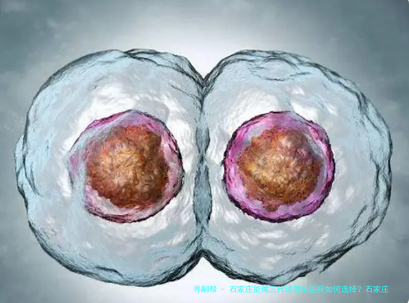

石家庄三代试管婴儿成功率

石家庄地区三代试管的成功率在50%-60%左右,每个医院的成功率可能不同。